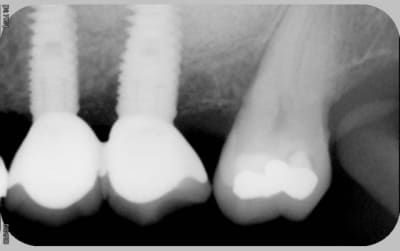

16/06/2010 à 16h05

comme promis

voici les cas vus ce mardi (il me manquait encore 10 patients: sur les 5 autres, tout est ok)

ps: la carie et le tartre sur la 7 ont été traités